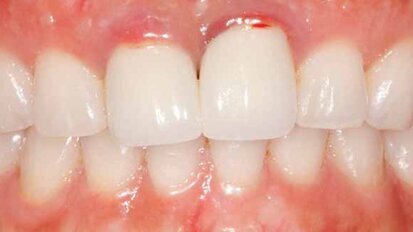

Let patients test-drive their new smiles

The decision to pursue ceramic dental restorations is a major one for most patients. There may be a concern that the results will turn out to be different ...